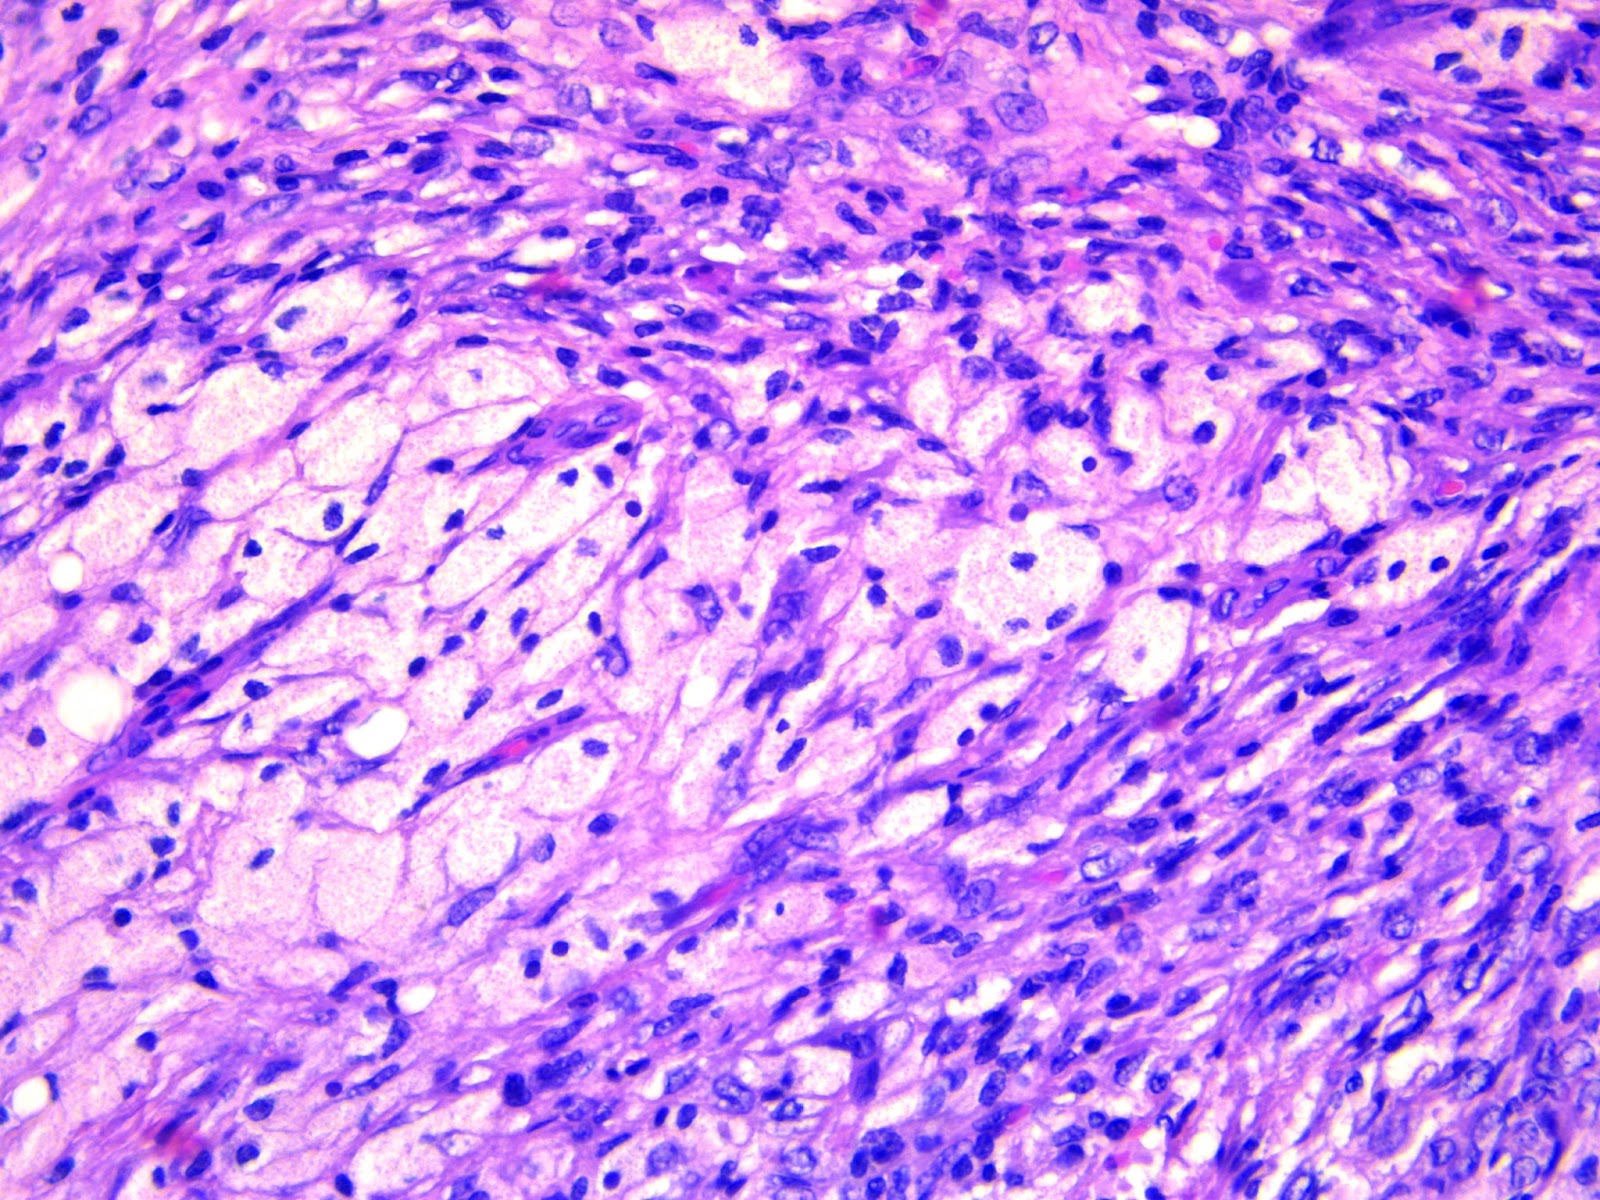

From www.orthobullets.com

NonOssifying Fibroma Pathology Orthobullets Radiology Non Ossifying Fibroma It is considered a type of fibrous xanthoma of bone and is identical to fibrous cortical defect (fcd), which occurs in younger children. However, prophylactic curettage and bone grafting. Nonossifying fibroma is a common benign finding encountered in the practice of radiology. Fibroxanthomas can be divided into: Fibrous cortical defect (fcd) is a fibroxantoma smaller than 2 cm. Nof is. Radiology Non Ossifying Fibroma.